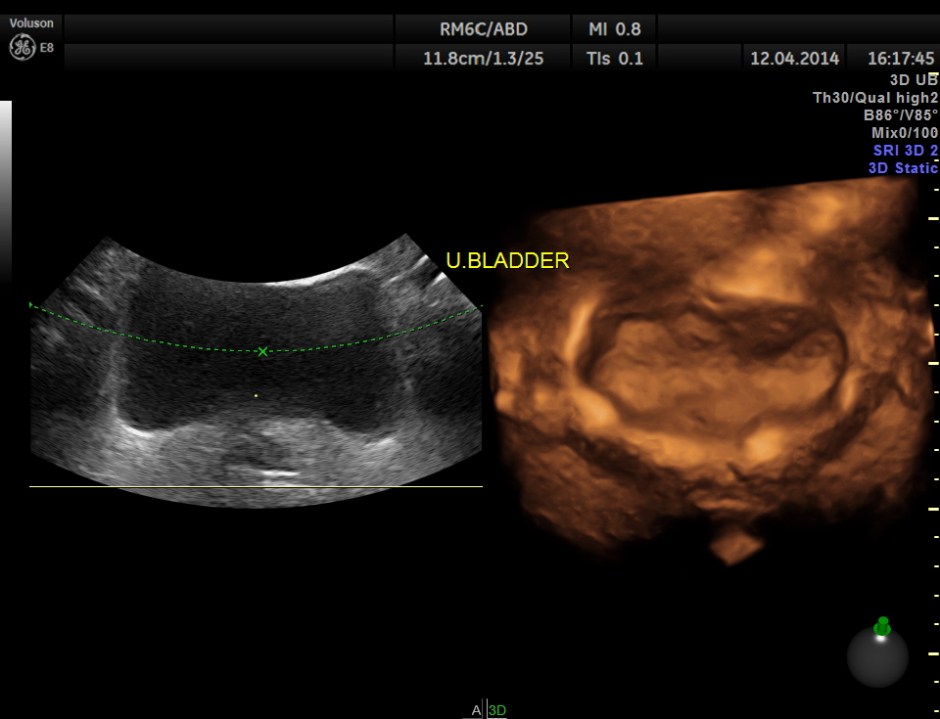

Urinary bladder wall was mildly thickened . 3D showed fairly normal bladder mucosa . Ureteric jets were seen normally.

The distal ureters were not visualised .